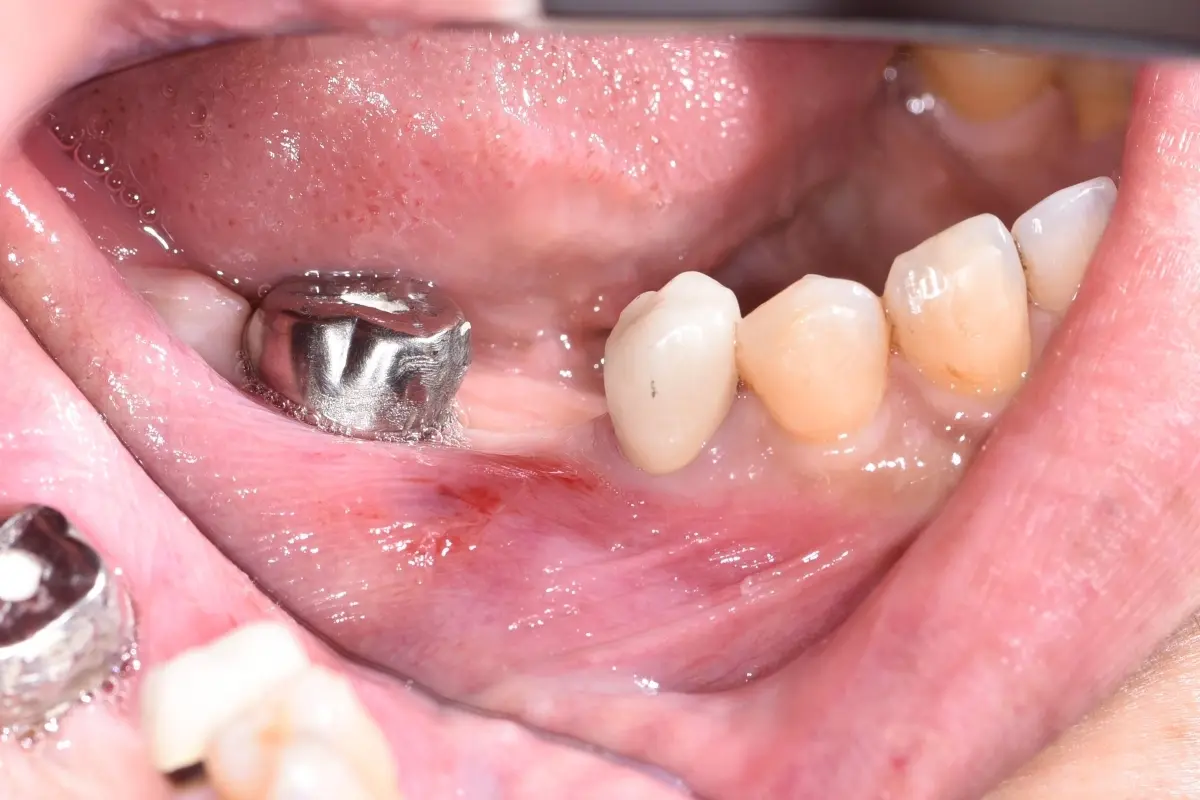

牙橋

主治醫師

• 楊明憲

治療時間

約1年4個月

主訴

吃東西左邊後牙會痛